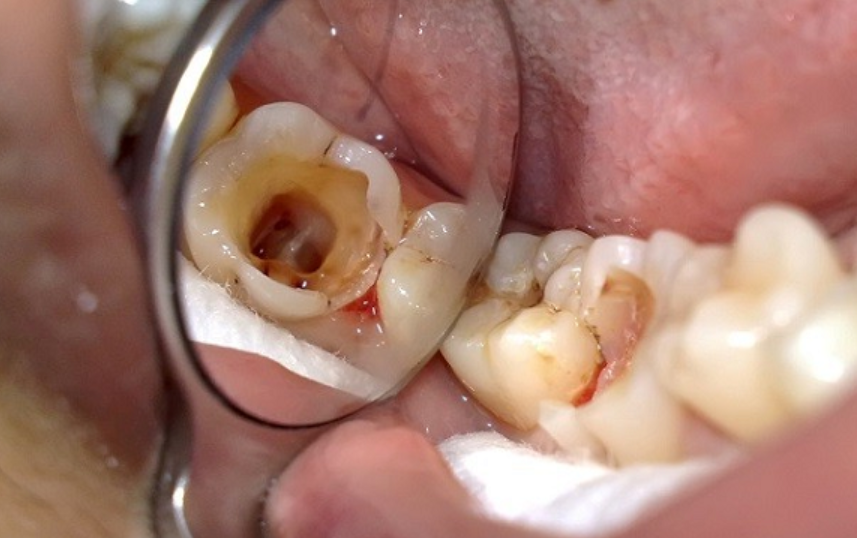

Răng, một phần quan trọng trong hệ thống tiêu hóa, đóng vai trò quan trọng trong việc nuôi dưỡng toàn bộ cơ thể. Tủy răng, với dây thần kinh và mạch máu phong phú, chịu trách nhiệm không nhỏ trong quá trình tái tạo ngà răng và duy trì sự sống của răng. Việc điều trị tủy răng là một bước quan trọng để bảo vệ sức khỏe răng miệng. Tủy Răng Là Gì? và Nguyên Nhân Viêm Tủy Răng: Tủy răng, nằm ở buồng tủy và ống tủy, là nguồn cung cấp dinh dưỡng quan trọng cho răng. Tình trạng viêm tủy răng có thể xuất phát từ nhiều nguyên nhân, như răng bị mẻ vỡ, sâu răng lâu ngày, chấn thương, hoặc răng bị mòn, viêm quanh răng. Đối diện với những vấn đề này, việc điều trị tủy răng kịp thời trở nên cực kỳ quan trọng. Tác Dụng của Việc Điều Trị Tủy Răng: Điều trị tủy răng không chỉ giúp giảm đau mà còn ngăn chặn sự lây lan và mất răng, ngăn chặn các biến chứng nguy hiểm như viêm quanh chóp, áp xe quanh chóp, nhiễm trùng máu. Điều trị tủy răng kịp thời còn giúp ổn định khả năng ăn nhai và duy trì sự sống của răng. Điều Trị Tủy Răng tại Nha Khoa 3C: Tại Nha Khoa 3C, chúng mình cam kết mang đến quy trình điều trị tủy răng an toàn và hiệu quả nhất cho khách hàng: 1. Thăm Khám và Chụp X-quang: Nha khoa 3C bắt đầu mọi điều trị bằng việc thăm khám và chụp X-quang để đánh giá mức độ viêm nhiễm và lên kế hoạch điều trị chi tiết. 2. Vệ Sinh Răng Miệng và Gây Tê: Trước khi bắt đầu điều trị,